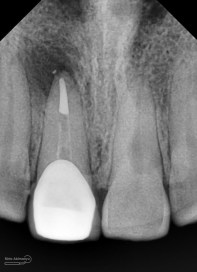

dan ini hasil ronsen final…

Foto radiografis akhir

Terlihat padat dan hermetis dari ujung sampai ke crown….

Nah ini resume foto2 nya untuk perbandingan